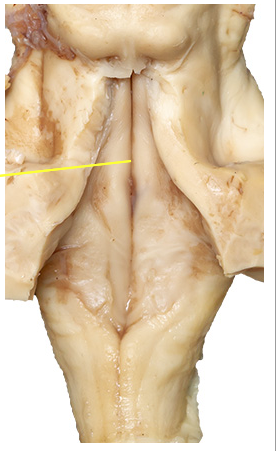

What is the yellow line pointing at?

hypoglossol trigone

median sulcus

The obex - rostolaterally near it is the area postrema the chemoreceptive emetic centre